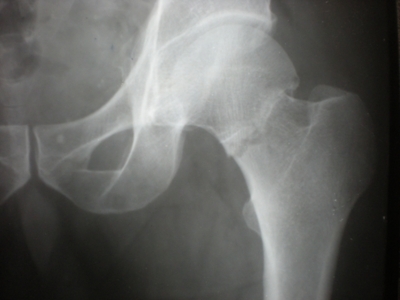

Quel diagnostic? Quelle doit être la déformation clinique du membre inf? Doit-on la réduire?

A

Fracture de l’ES du fémur gauche Garden 1

coxa valga

engrènement du foyer de fracture= stable = pas de réduction